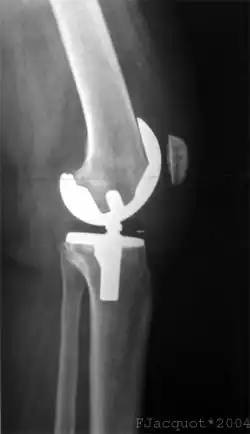

Standardverfahren ist weiterhin die Kreuzbandplastik mit Einsatz eines autologen (körpereigenen) oder Allograft- (von einem menschlichen Spender stammenden) Sehnenimplantats, das das Kreuzband möglichst anatomisch exakt ersetzt.[145]

Kreuzbandplastik

Am Häufigsten werden die Operationstechniken einer Rekonstruktion des gerissenen Kreuzbandes durchgeführt. Die Reste des zerrissenen Bandes werden dazu femoral komplett und tibial mit gutem Rest entfernt und durch ein neues Band ersetzt. Das neue Band kann aus körpereigenem Gewebe (autolog) oder aus dem Gewebe von Verstorbenen (allogen) oder einer anderen Spezies (xenogen) sein.[16]

Bei der Rekonstruktion des Kreuzbandes mittels autologer Transplantation der Kniescheibensehne wird diese mit anhängenden Knochenteilen entnommen und durch verbreiterte Kanäle (8–10 mm Durchmesser) im Schienbein beziehungsweise Oberschenkelknochen gezogen. Die Länge des oberen und unteren Knochenblocks beträgt jeweils etwa 20 mm. Die stabilste Verankerung der Knochenenden des autologen Transplantats (englisch graft = Transplantate ohne Blutversorgung, weshalb sowohl hier als auch bei der im folgenden Abschnitt näher erläuterten Semitendinosustechnik von autograft gesprochen wird, mit altgriechisch αὐτός = selbst) wird durch die Fixation mit sogenannten Interferenzschrauben erreicht. Diese ist besonders wichtig im Hinblick auf eine frühe funktionelle Mobilisierung.